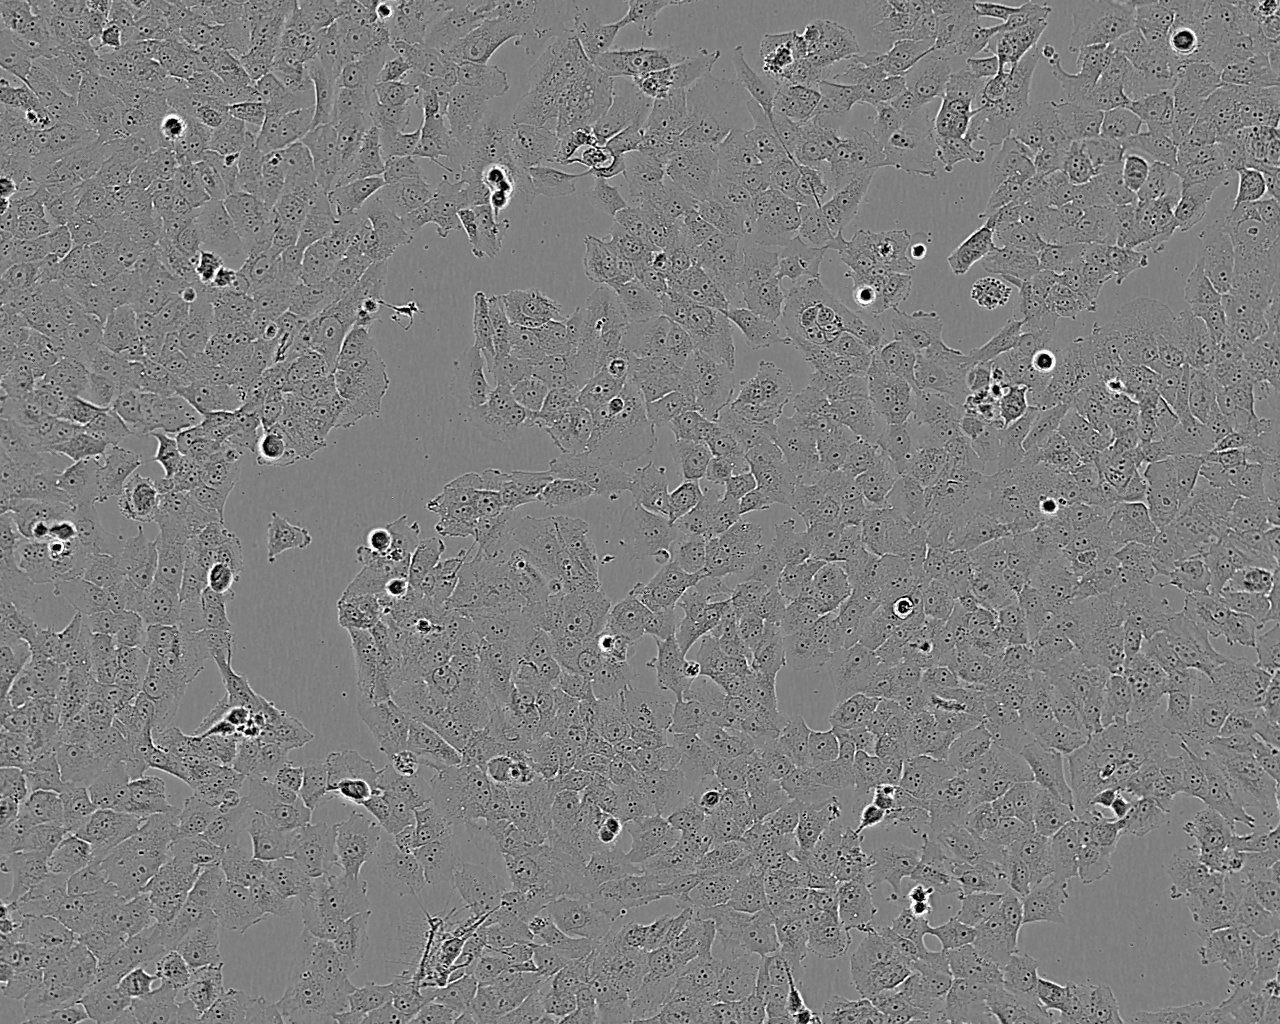

NCI-H1792细胞:人肺癌腺癌细胞系

细胞形态:上皮细胞样

细胞生长:贴壁

细胞生长特性:贴壁生长